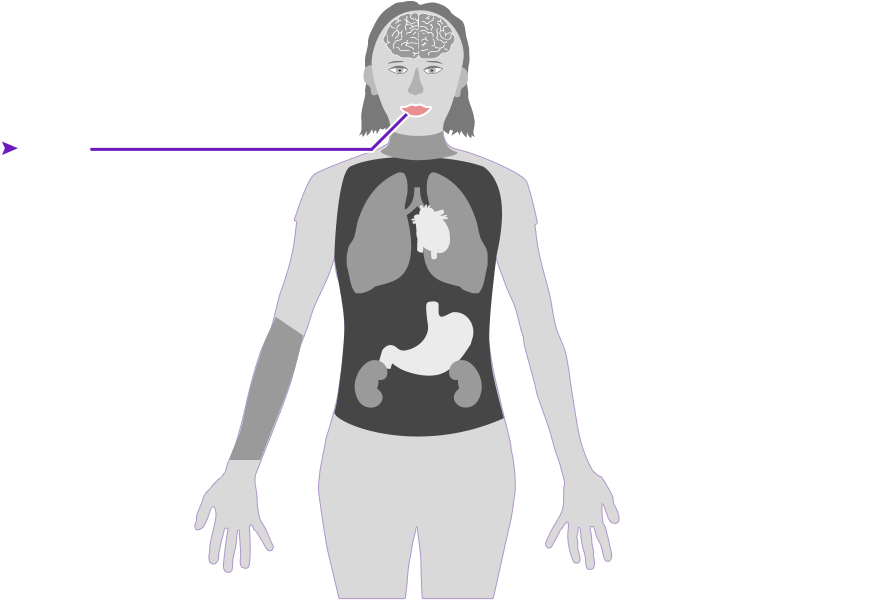

Check out how mercury can affect the human body. Click on the different parts of the body to see what can happen when people are poisoned by mercury. How serious these health effects are may vary depending on how much mercury gets into your body — and how long you breathe it in.

Health effect caused by breathing in high levels of mercury vapors (fumes) over a short period of time

Health effect caused by breathing in high levels of mercury vapors (fumes) over a short period of time  Health effect caused by breathing in lower levels of mercury vapors over a long period of time